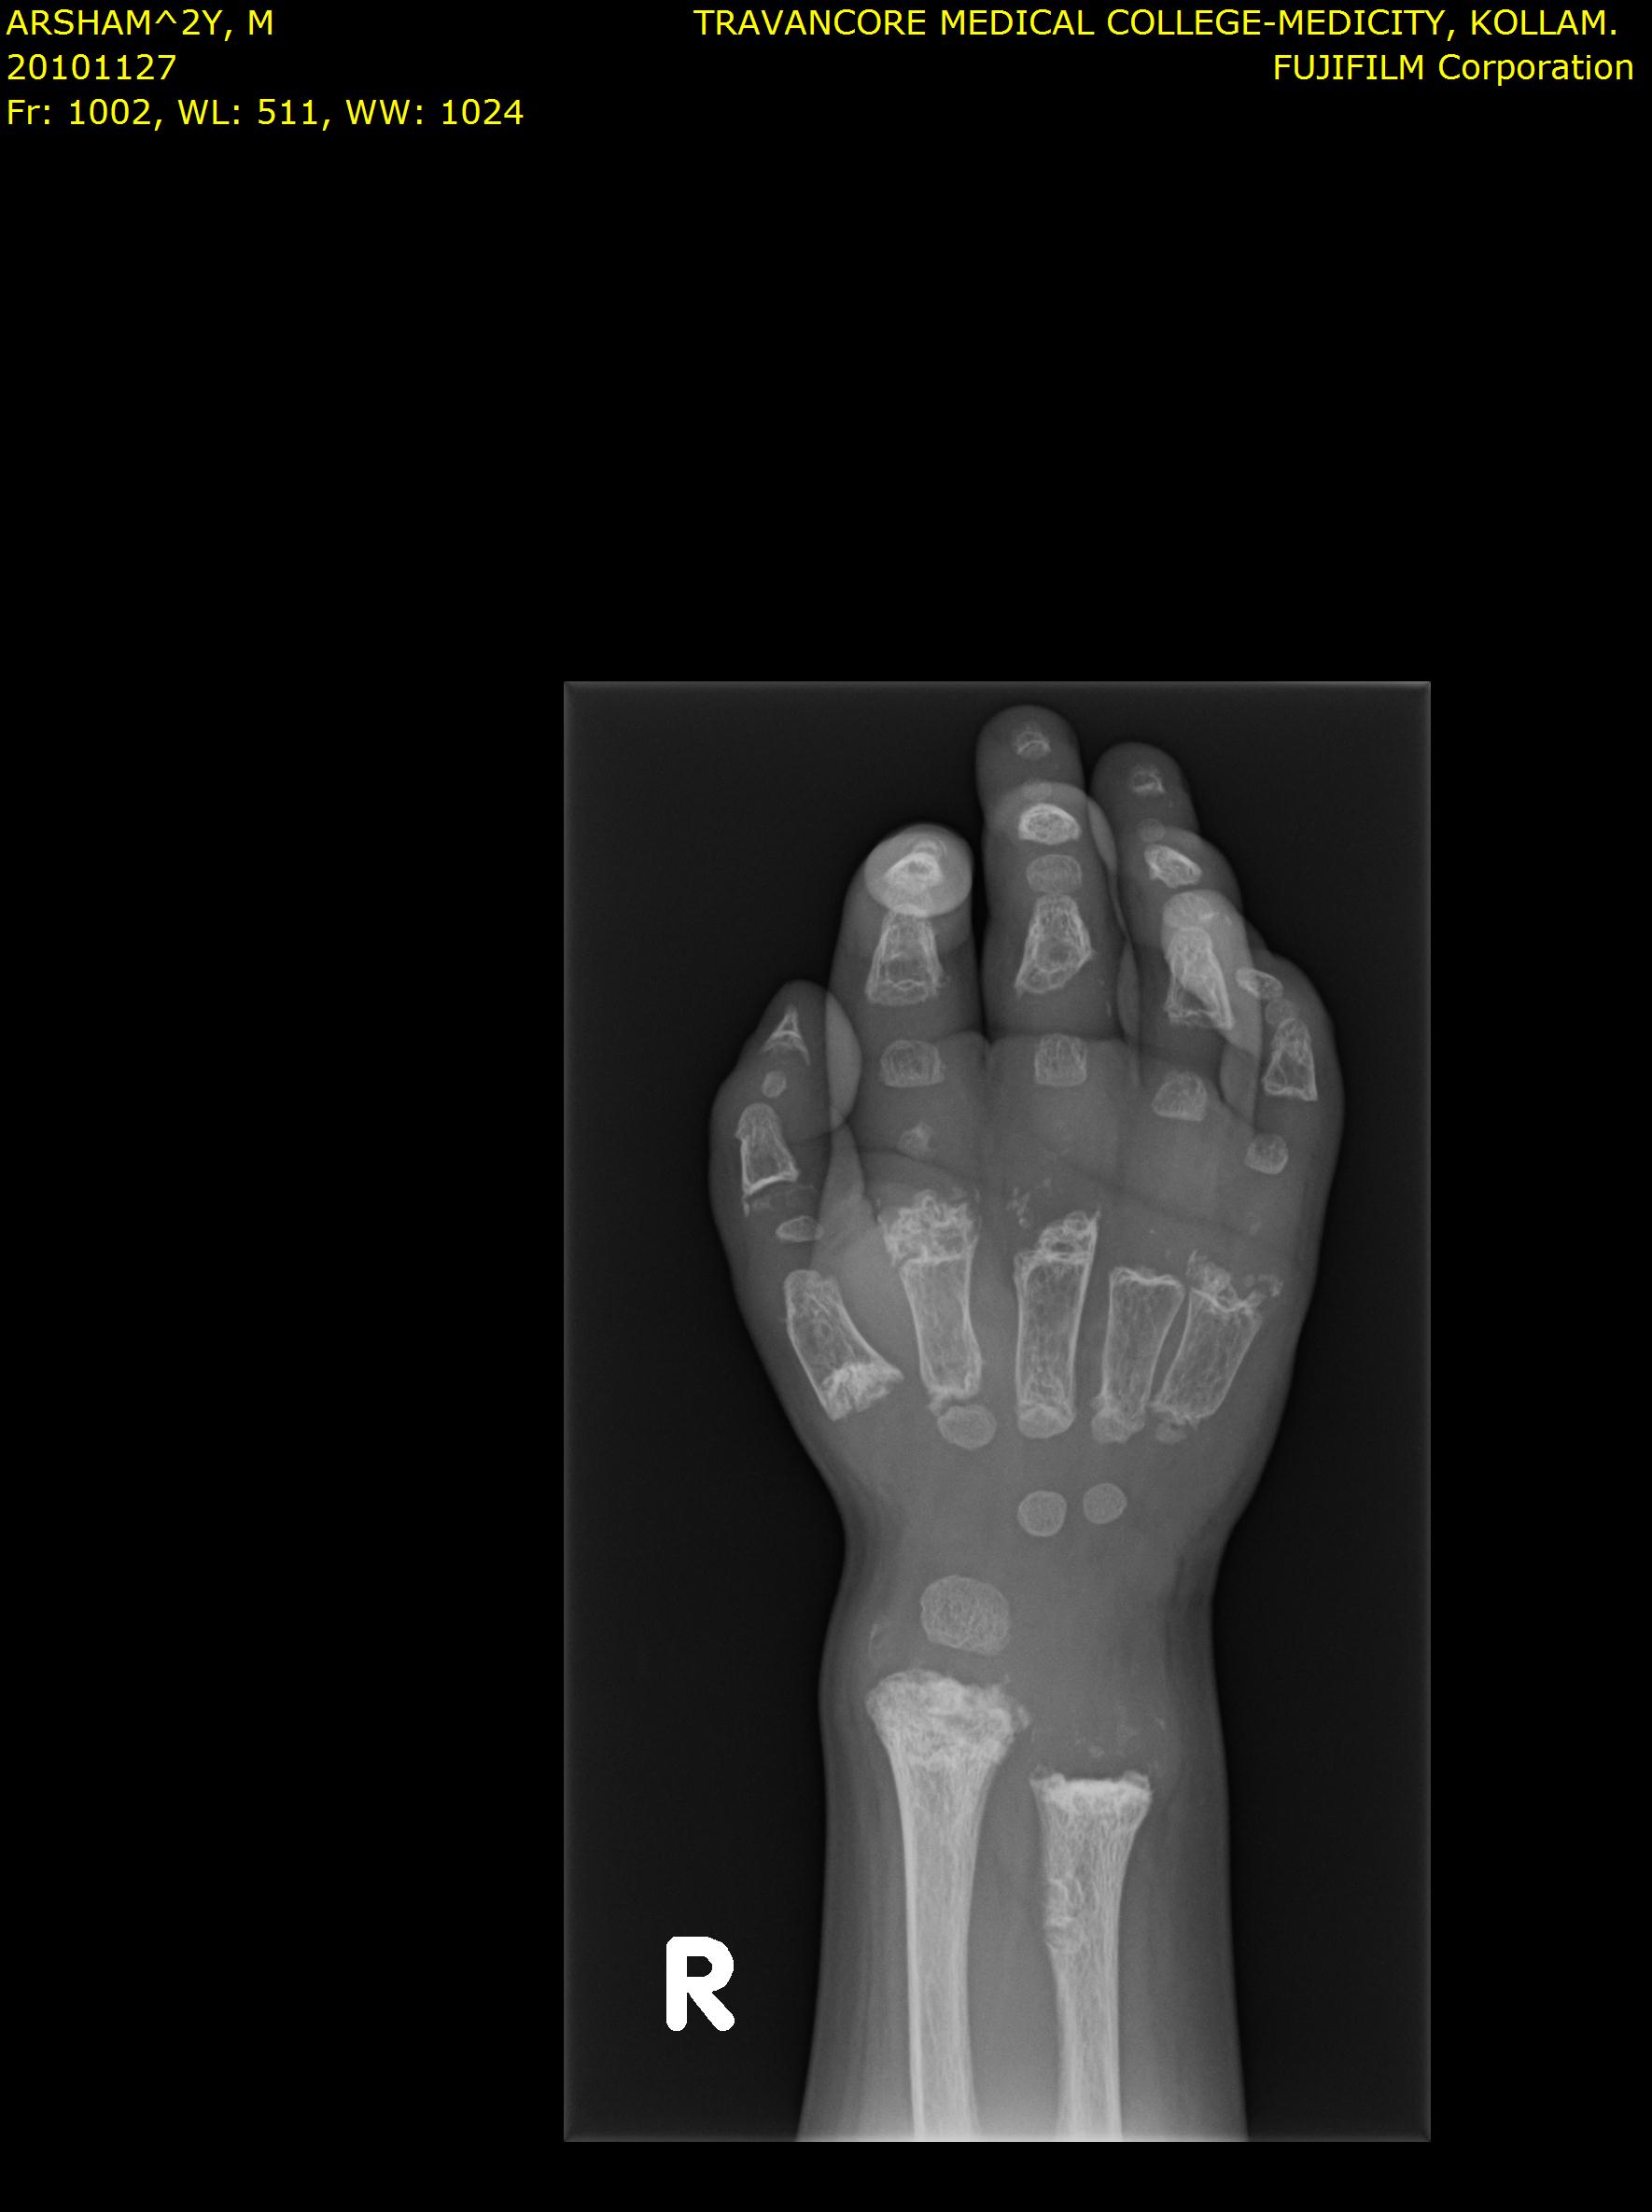

Here we share radiographic images to help with diagnosis of Jansen's disease:

Skull X-ray showing features of Jansen's disease Spine X-ray showing skeletal abnormalities Foot X-ray showing bone changes Additional foot X-ray Hand X-ray showing clinodactyly Additional hand X-ray Hands X-ray showing short distal phalanges Radiographic image associated with Jansen's disease

Jansen's patients show extreme disorganization of the metaphyses of the long bones and of the metacarpal and metatarsal bones in sharp contrast to the almost normal appearance of the epiphyseal centers, which on x-ray appear widely separated from the long bones. The chin is receding. The fingers, especially the distal phalanges, are very short. The spine, pelvis, and lower legs are distorted.